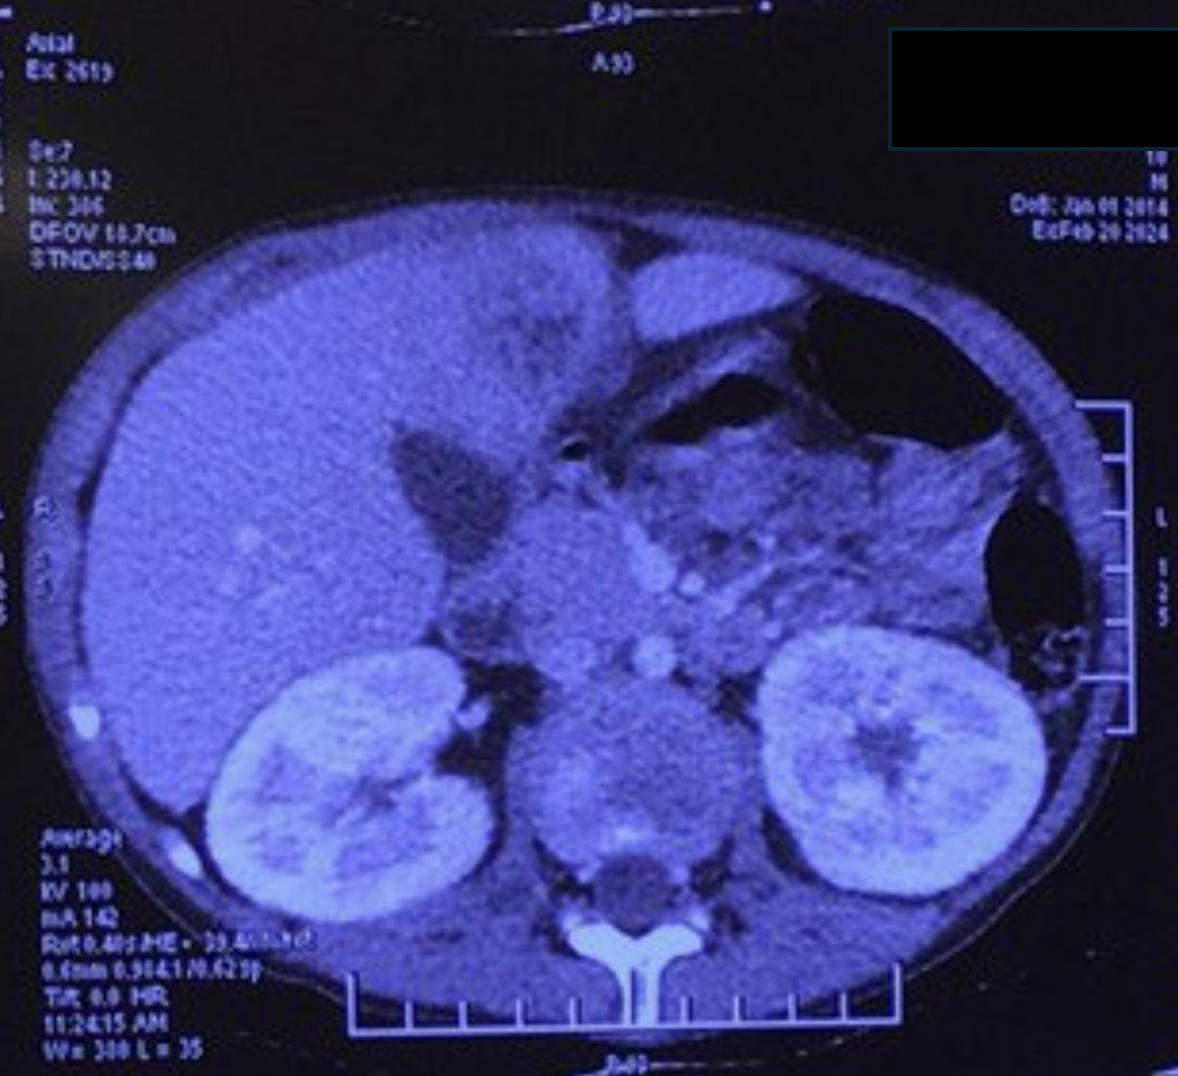

Four weeks later, he developed right upper quadrant abdominal pain associated with hepatomegaly and hepatic tenderness. Contrast-enhanced abdominal CT showed two well-circumscribed space-occupying lesions in segments 7 and 4B of the liver with estimated volumes of 50 mL and 35 mL, respectively (Figure 1). Post-contrast enhancement of the edematous peripheral rim was observed. A partially liquefied liver abscess was suspected; aspiration was not attempted due to refractory thrombocytopenia.

He was started on conditioning with fludarabine, cyclophosphamide, and anti-thymocyte globulin with 4 Gy total body irradiation for haploidentical HSCT (father as the donor) under coverage with the same antibiotics. Neutrophils engrafted on day 12, following which his fever improved. The timeline of infection and absolute neutrophil count is shown in Figure 2. The liver abscess showed clinical resolution with regression of fever and hepatomegaly. On repeat imaging, there was resolution of the abscess in segment 4B and regression in segment 7. The patient, however, developed steroid-resistant acute graft-versus-host disease with refractory diarrhea and died on day 74 post-HSCT.